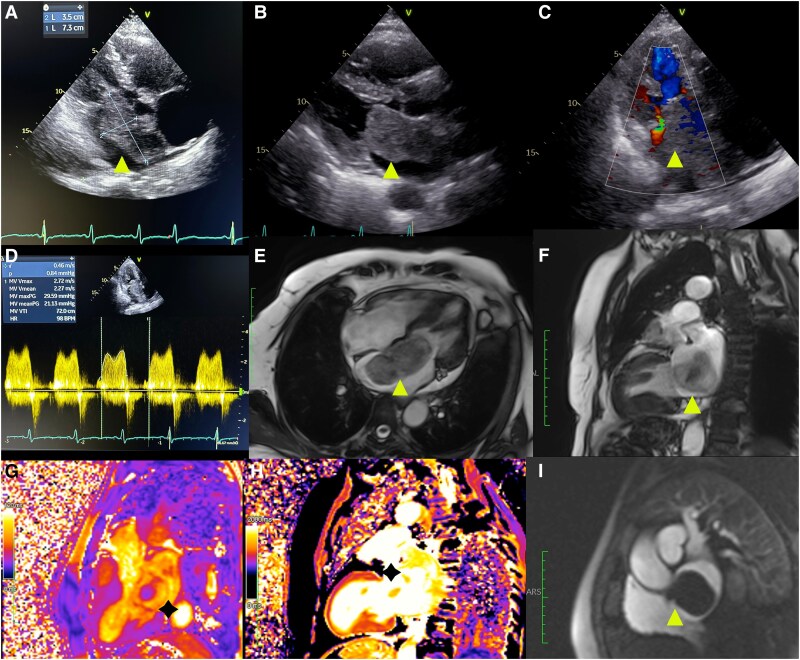

An unanticipated cause of worsening dyspnoea: mitral stenosis induced by cardiac myxoma.